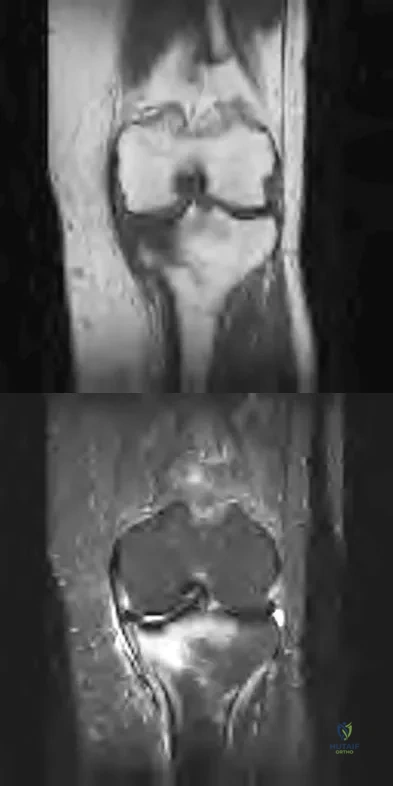

Question 82

Figures 43a and 43b show the T1- and T2-weighted MRI scans of a 78-year-old woman who reports the sudden atraumatic onset of well-localized medial knee pain. Pain is worse at night and also occurs with weight-bearing activity. What is the most likely diagnosis?

Explanation